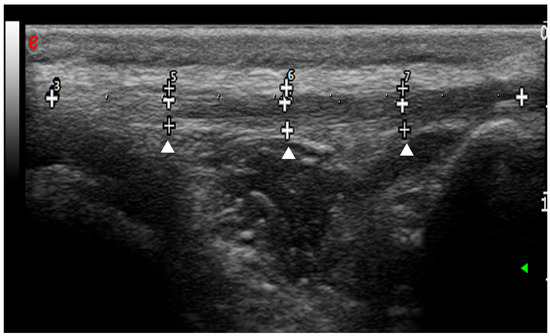

2.4. Ultrasonographic and Strain Elastosonographic Evaluations

- Pennasilico, L.; Volta, A.; Sassaroli, S.; Di Bella, C.; Riccio, V.; Pilati, N.; Tambella, A.M.; Dini, F.; Palumbo Piccionello, A. Ultrasound and elastosonographic features of the patellar ligament in dogs affected by cranial cruciate ligament disease. Vet. Sci. 2024, 11, 126. [Google Scholar] [CrossRef]

- Palumbo Piccionello, A.; Serrani, D.; Busoni, V.; Salvaggio, A.; Bonazzi, M.; Bergamino, C.; Volta, A. Sonoelastographic features of the patellar ligament in clinically normal dogs. Vet. Comp. Orthop. Traumatol. 2018, 31, 279–284. [Google Scholar] [CrossRef]